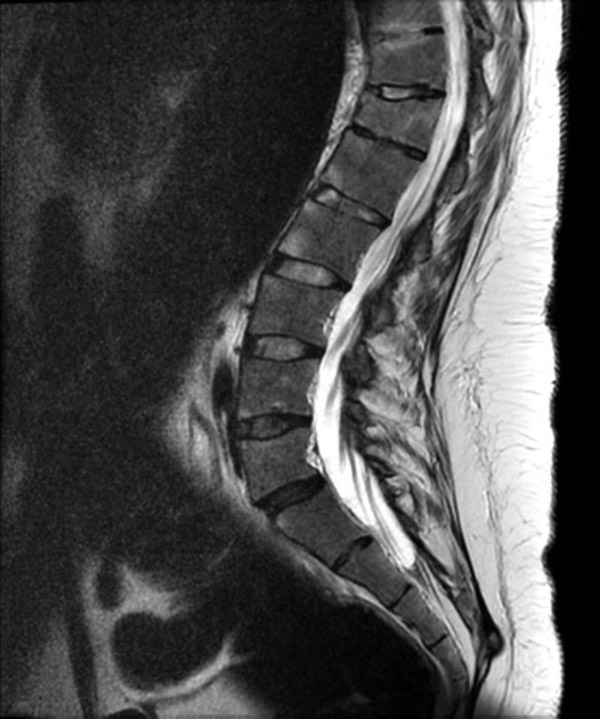

Chụp cộng hưởng từ (MRI) là kỹ thuật chẩn đoán hình ảnh không xâm lấn, cho phép tạo ra hình ảnh chi tiết các cấu trúc bên trong cơ thể, bao gồm các cơ quan, xương, cơ và mạch máu. Máy MRI là một thiết bị lớn, hình trụ, sử dụng từ trường mạnh và sóng radio để tạo ra hình ảnh, không sử dụng bức xạ ion hóa như chụp X-quang.

Từ trường này khiến các nguyên tử trong cơ thể sắp xếp theo cùng một hướng. Sau đó, máy phát ra các xung sóng radio, làm thay đổi hướng của các nguyên tử này. Khi sóng radio tắt, các nguyên tử trở về vị trí ban đầu và phát ra tín hiệu radio. Các tín hiệu này được máy vi tính xử lý để tạo ra hình ảnh chi tiết của bộ phận cơ thể cần khảo sát. Hình ảnh này được hiển thị trên màn hình để bác sĩ quan sát và phân tích.

Chụp MRI có thể được sử dụng để chẩn đoán các vấn đề về khớp, gồm:

Sau đây là một số hình ảnh viêm cột sống dính khớp trên X-quang: